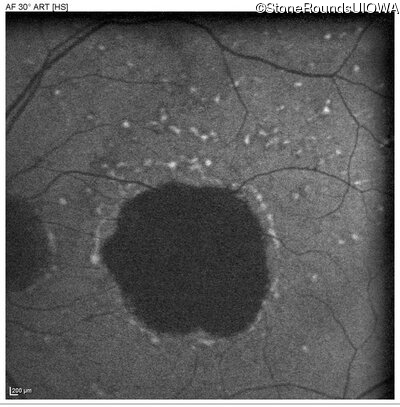

Pattern Dystrophy (IIC)

Age at visit: 47 years

This 47 year man first experienced some decrease in his central vision about 10 years ago.